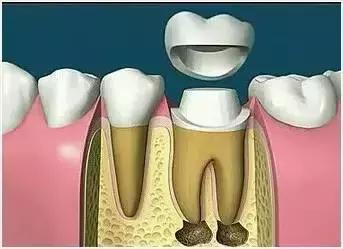

7、根管打桩

因牙体缺损过多,导致牙的强度(承受力量的性能)大幅度下降,不能很好地承受咀嚼力量。打桩的目的是增加牙根及牙冠的强度,增加患牙的稳固。

8、完成牙体修复

X线片显示根管充填完好,行暂时或永久牙体修复,带上牙冠,保护患牙。至此根管治疗才可算完成,同时根管治疗后还需复诊,一般周期可为3个月、半年、1年、2年或更长。